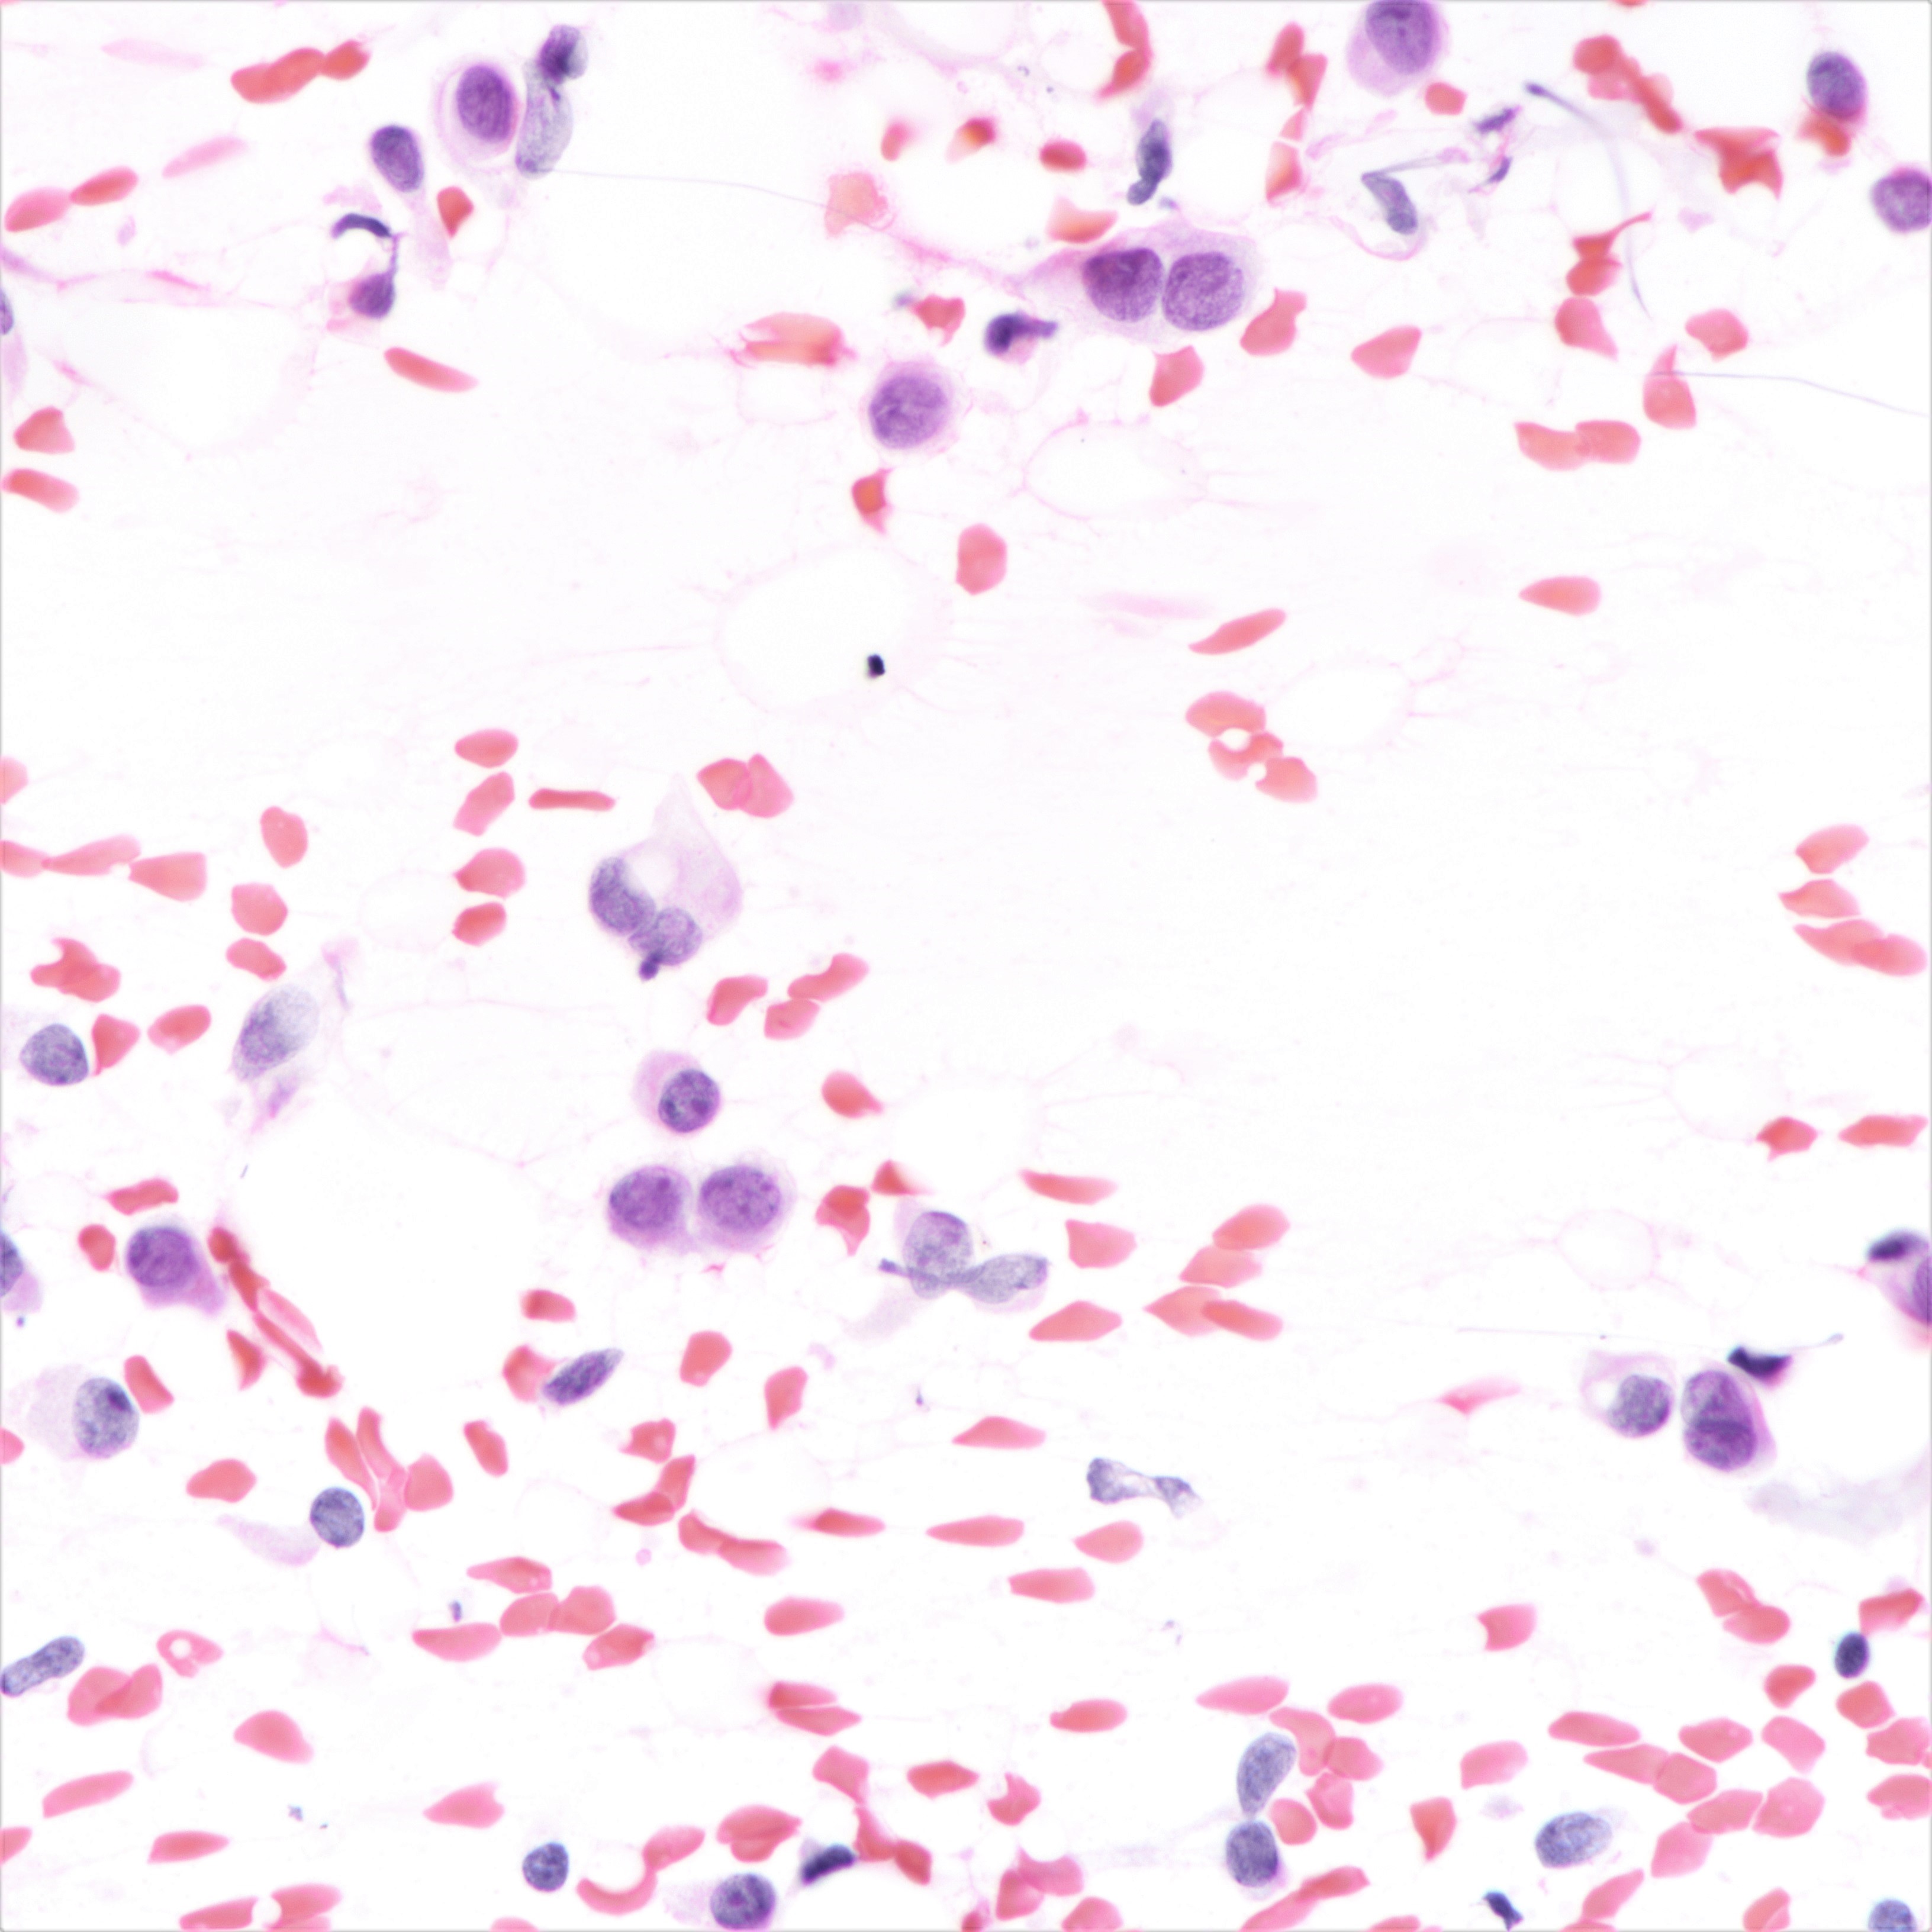

Cytology description

- Cellularity can be low

- Tumor cells arranged in chains, single files or as single cells

- Tumor cells arranged in small chains are helpful clues

- Nuclear atypia mostly mild

- Nuclei round to oval and eccentric

- Cytoplasm scanty with a high nuclear / cytoplasmic ratio

- Occasional intracytoplasmic vacuolations may be seen

- Cytologic features can resemble mesothelial cells in effusion fluid (Diagn Cytopathol 2012;40:311)

Cytology images